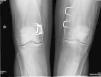

Observación clínicaSe trata de un varón de 58 años, enviado a la consulta externa de Reumatología por sospecha de fragilidad ósea. A los 6 años de edad había sido intervenido de genu valgo bilateral marcado, sospechándose entonces una osteopatía congénita. La intervención mejoró la estática de sus miembros inferiores y el paciente pudo realizar una vida normal, sin procesos patológicos relevantes, hasta los 57 años, cuando, tras un traumatismo de baja intensidad, sufre una fractura de clavícula y cotilo izquierdos. En la anamnesis efectuada no se recogieron factores de riesgo de osteoporosis ni antecedentes familiares o personales de interés, excepto la intervención quirúrgica comentada. En la exploración física se trataba de un adulto con buen aspecto general, sin deformidades craneofaciales, con un moderado genu valgo bilateral y las limitaciones propias de las fracturas recientes, para las que precisó tratamiento quirúrgico. Presentaba una talla de 182cm, con 81kg de peso (IMC 24,45kg/m2), resultando el resto de la exploración física irrelevante. Los análisis generales resultaron normales, con cifras de calcio iónico sérico de 2,41mmol/l, fosfatasa alcalina total de 115u/l, 25-OH-D3 de 32,8ng/ml y PTHi de 56pg/ml. La densitometría ósea mostró un T-score de −1,4DE en columna lumbar (928mg/cm2) y de −2,2DE en cuello femoral (625mg/cm2). En el estudio radiográfico realizado se objetivó un patrón característico de la EP, con un ensanchamiento metafisario de los huesos tubulares (fig. 1), un marcado adelgazamiento cortical y normalidad en la morfología epifisaria.

DiscusiónNuestro paciente cumple las características radiográficas de la EP en el adulto, que incluyen una expansión metafisaria de los huesos largos y un marcado adelgazamiento cortical8,9. Todos los huesos largos pueden estar afectados, aunque los hallazgos característicos son más evidentes en la tibia proximal y en el fémur distal (con el típico aspecto en «matraz de Erlenmeyer»). Los huesos craneofaciales pueden verse afectados con cambios discretos y ocasionales, como osteoesclerosis parcheada y obliteración de los senos paranasales. No obstante, cuando estas alteraciones son marcadas deben descartarse otras enfermedades hereditarias, sobre todo la displasia craneometafisaria, que comparte con la EP el modelado anormal metafisario, pero se diferencia claramente ya que los pacientes afectados presentan una facies muy peculiar, con hipertelorismo y engrosamiento del puente nasal, y no tienen afectación de clavículas, costillas y ramas isquiopubianas. La enfermedad de Camurati-Engelmann también se incluye en el grupo de las displasias metafisarias, pero, a diferencia de la EP, provoca hiperostosis en la base del cráneo y engrosamiento cortical en los huesos largos. Otros procesos a considerar en el diagnóstico diferencial de la EP son las osteopetrosis, en las que, además del aumento de densidad ósea que caracteriza al grupo, se aprecian imágenes de «hueso dentro de hueso» tanto en los cuerpos vertebrales como en las regiones diafisometafisarias de los huesos tubulares. Otras enfermedades a tener en cuenta en el diagnóstico diferencial son la enfermedad de Gaucher, la de Niemann-Pick y las talasemias, aunque son fácilmente descartadas por la historia clínica y las pruebas complementarias, así como por la ausencia de afectación extraósea y la normalidad de las pruebas de laboratorio que se observan en la EP.